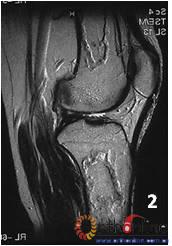

2. 发生在骨端(股骨头、肱骨头等)的坏死称为骨坏死(osteonecrosis,ON)。ON有两种类型:单纯骨髓坏死,软骨下骨(皮质骨)部分保留;骨髓坏死连同皮质坏死。

图 3 男,53岁,激素相关股骨头坏死,MRI(2003年)示右侧L1型坏死(皮质存留,骨髓坏死),左侧L3型坏死(皮质及骨髓均坏死),三年后(2006年)及6年后(2009年),CT扫描示右侧股骨头维持圆形,骨皮质完整,但中央坏死灶未修复;左侧股骨头塌陷

Fig 3 Male, 53 year-old, steroid-associated ONFH, MRI(2003) showed type L1 necrosis(cortical bone was preserved, necrosis in bone marrow) in right side; type L3 necrosis(both cortical bone marrow) in left side. CT scan showed the right femoral head keep round, and collapse occurred in left femoral head three (2006) and six year (2009) later.

3. 两种类型的ON有不同的结局,前者预后较好,而后者预后差。(图3)